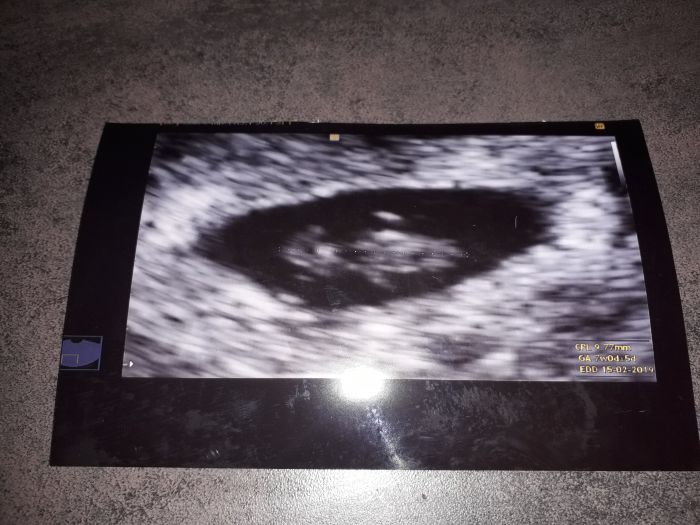

všechno je ok,jsem v 8 tt,bylo vidět i srdíčko

Peti 7+0,takže osmý..podle délky miminka,přesněji mi to dr poví po tom velkém utz.. zatím mám termín 15.2